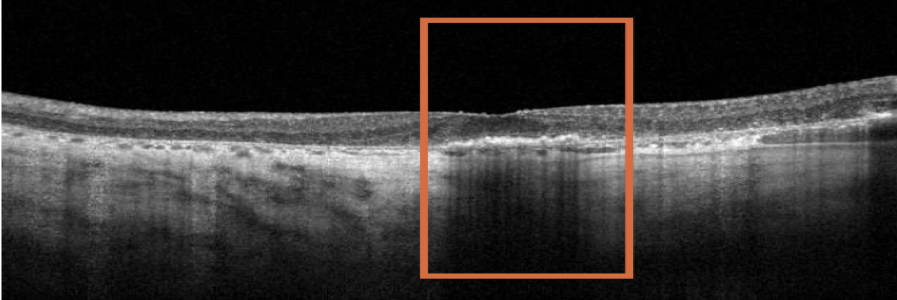

2 YEARS AFTER BASELINE VISIT

- BCVA: 6/12

- Visual function: Patient no longer feels comfortable driving although she is legally able to. Patient relies heavily on assistance from caregiver with some activities of daily living

Clear progression of perifoveal GA two years later.

OCT